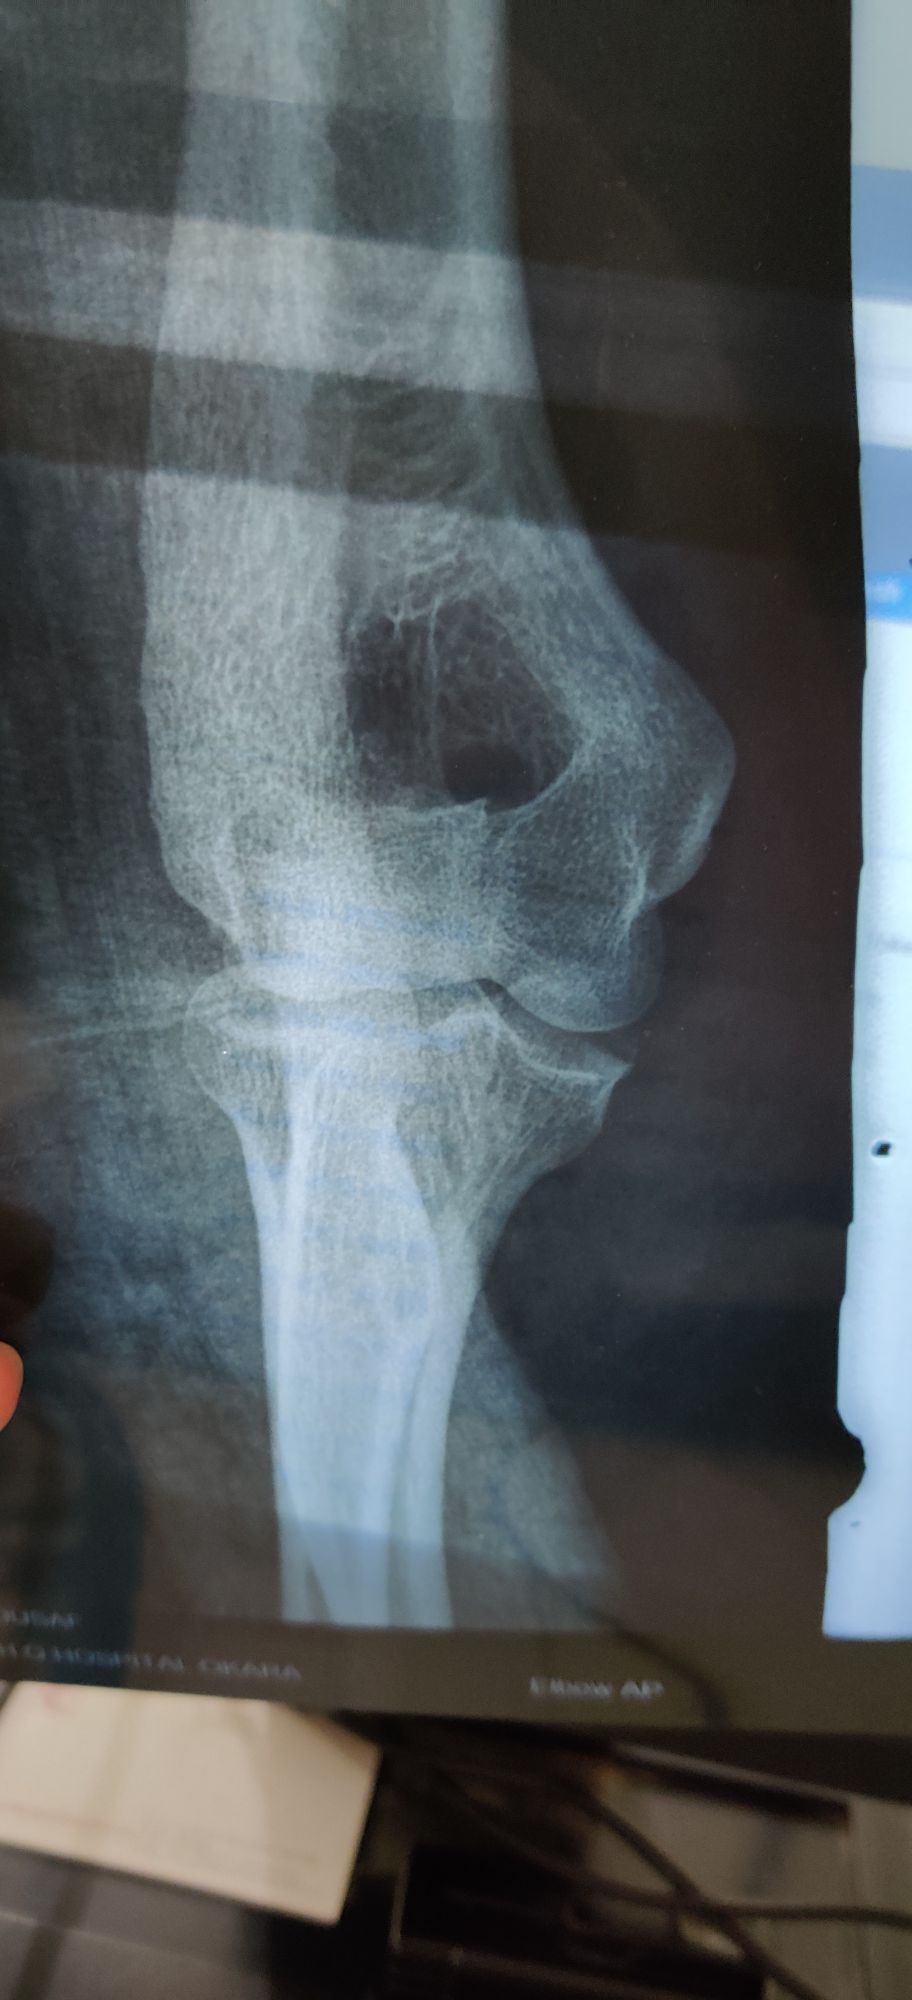

Fracture Olecranon?

Xray

Ortho

Elbow